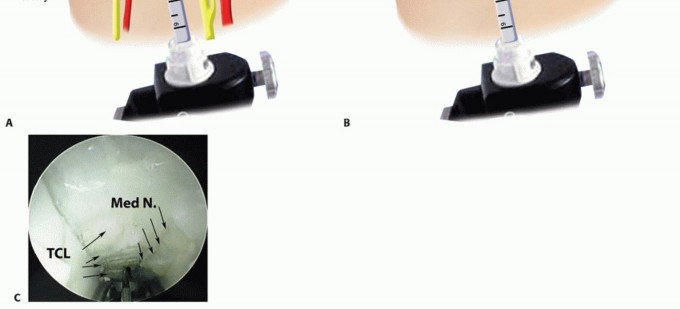

DEVICE INSERTION

TECH FIG 4 • The surgeon's nondominant index and long digits palpate the tip of the ECTR device as it emerges into the subcutaneous space just distal to the transverse carpal tunnel ligament. The transillumination pattern from the device light source changes from underneath the TCL to the midpalmar fat.

TRANSVERSE CARPAL LIGAMENT RELEASE